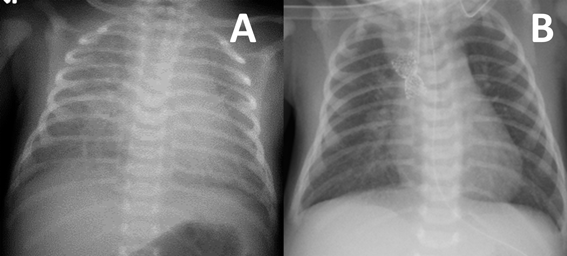

総肺静脈還流異常を合併した垂直静脈狭窄に対するステント留置中のバルーンエントラップメントEntrapment of a Balloon Catheter during Stent Implantation for Vertical Venous Stenosis in Two Neonates with Single Ventricle and Total Anomalous Pulmonary Venous Connection